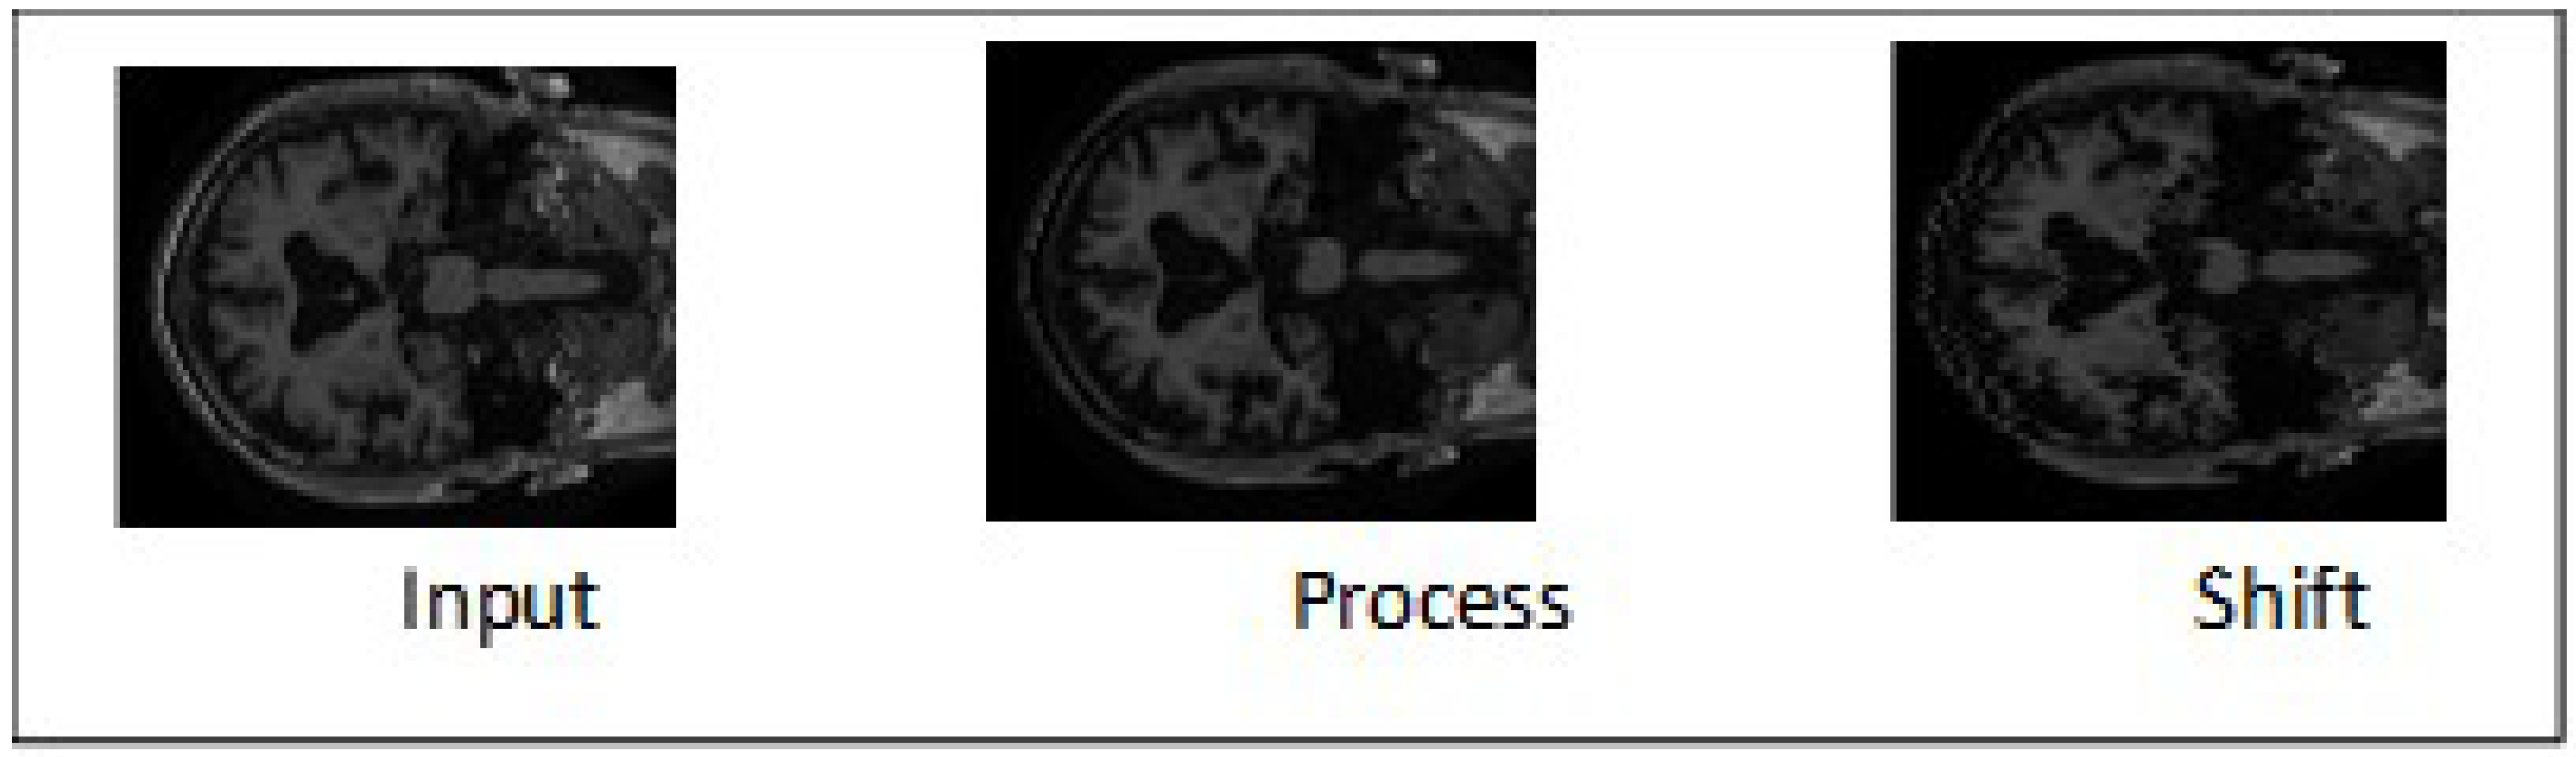

2.1. Preprocessing of MRI and PET Images

2.2. Proposed Fusion Technique of MRI and PET